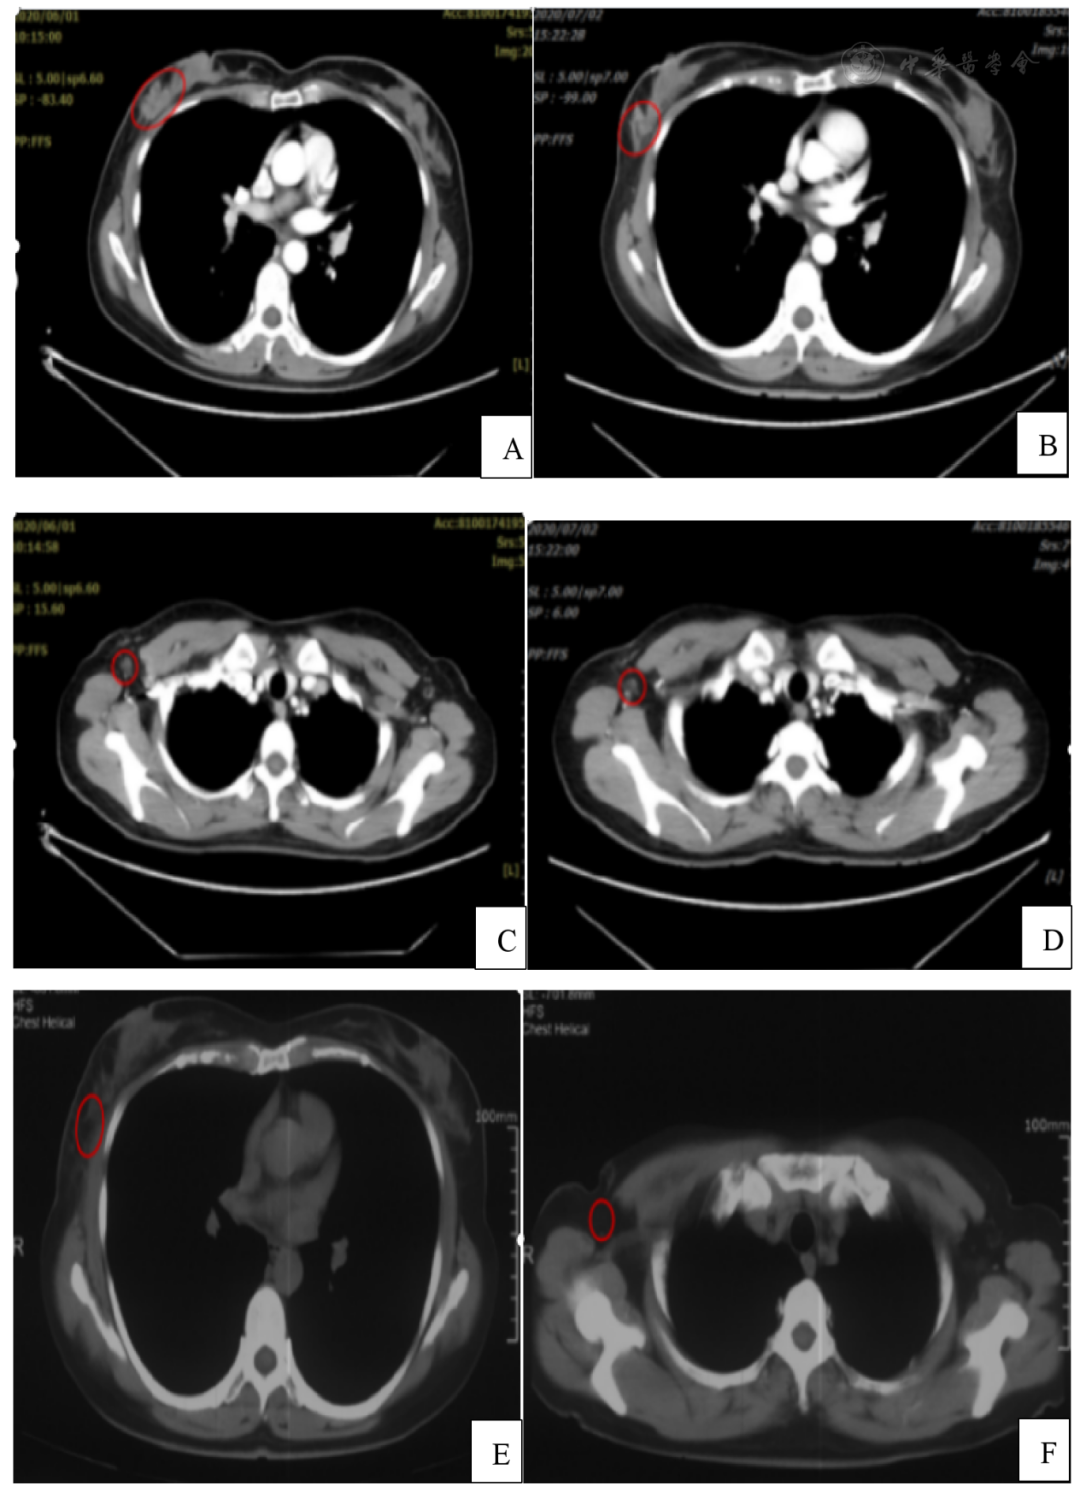

治疗完成后复查患者右乳原发病灶由2.5 cm×1.7 cm缩小至2.1 cm×1.2 cm( 图3A、B ),右侧腋窝转移淋巴结由1.2 cm×0.6 cm缩小至0.8 cm×0.5 cm( 图3C、D )。根据实体瘤疗效评价RECIST1.1标准:SD。根据RTOG放疗反应国际标准,治疗结束时患者右侧腋窝及乳腺皮肤轻度色素沉着,为1级急性皮肤反应。治疗结束后3周患者右侧腋窝及乳腺皮肤斑片状湿性脱皮,为2级急性皮肤反应。经过治疗后急性皮肤反应减轻并逐渐修复。其后按期随访,治疗结束后9个月复查胸部CT提示病灶完全消失,并无远处转移( 图3E、F ),根据实体瘤疗效评价RECIST1.1标准:CR。

图3 患者胸部CT

A:治疗前右乳原发灶;B:治疗后右乳原发灶;C:治疗前右侧腋窝转移淋巴结;D:治疗后右侧腋窝转移淋巴结;E:治疗后9个月右乳肿物消失;F:治疗后9个月右腋窝转移淋巴结消失